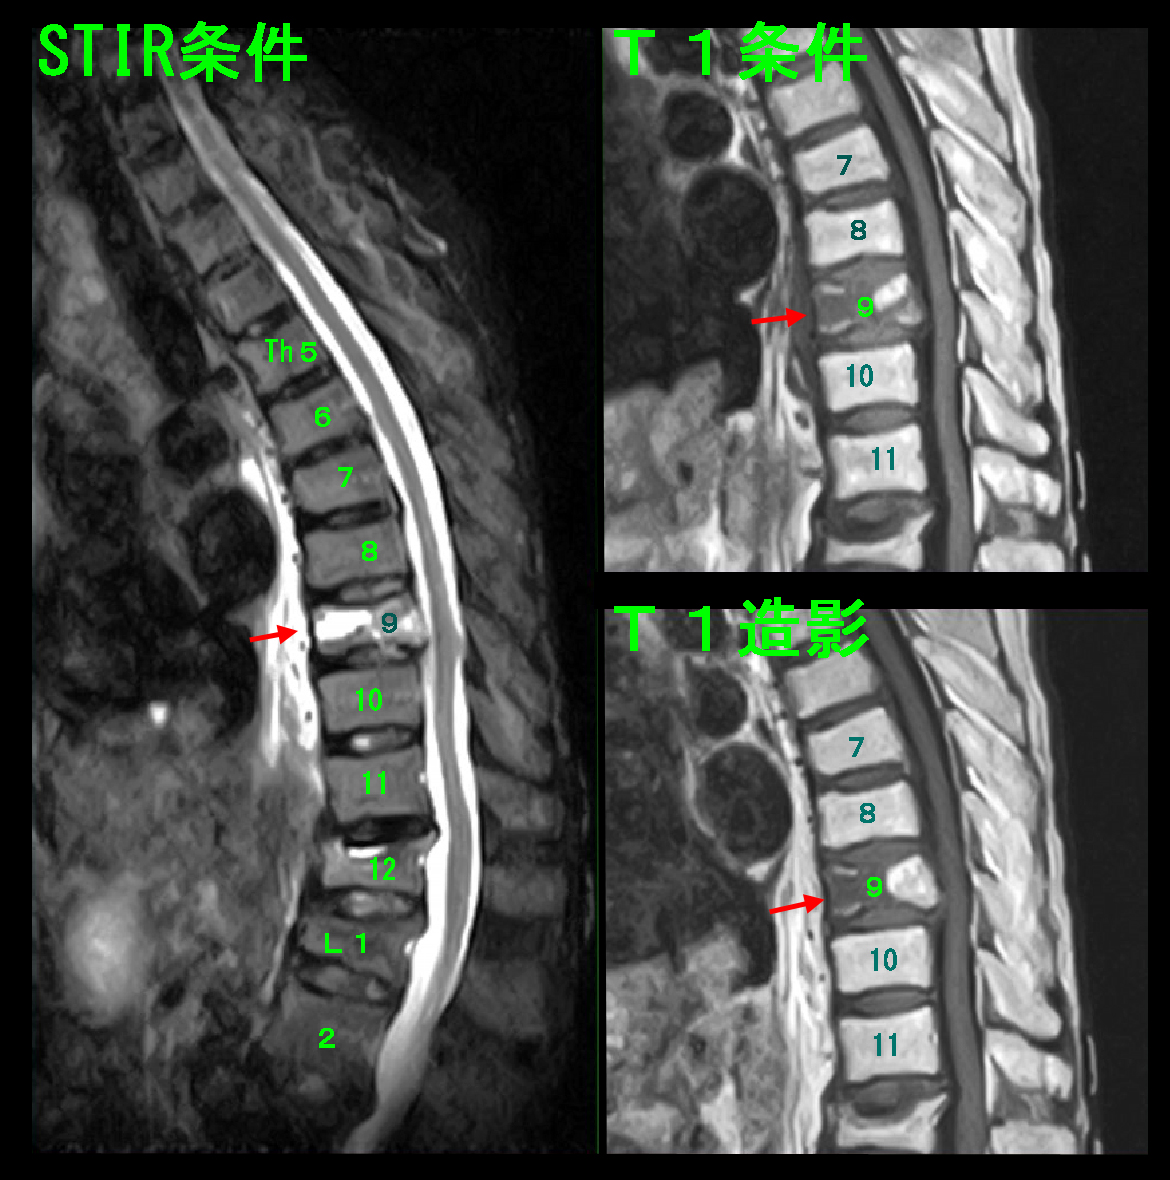

初診時の腰椎MRI検査では第12胸椎がつぶれために脊髄を圧迫するようになった所見が確認されました。

患者さんの腰痛は圧迫骨折発症後に続いているのですから、圧迫骨折により発症したTh11-12での脊髄圧迫が腰痛の原因であろうと推察しました。

初診時MRI検査を行って、第9胸椎(Th9)がSTIR条件で白く、T1条件では黒くなっており、骨折を示す所見であり、第9胸椎圧迫骨折と診断しました。コルセットも装着しましたが、2か月後の5月11日にはコルセットも外しています。